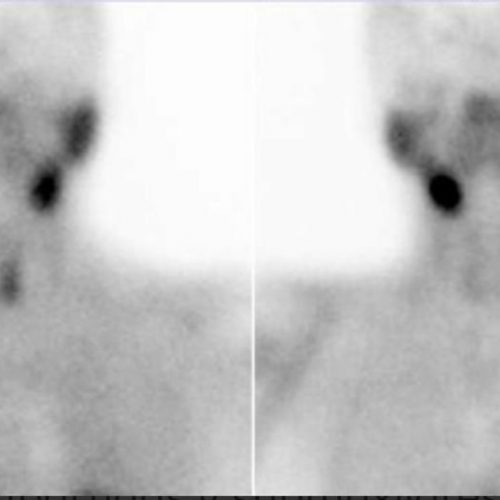

GAMMAGRAFÍA DE PARATIROIDES

Diagnóstico de adenoma o hiperplasia paratiroidea.